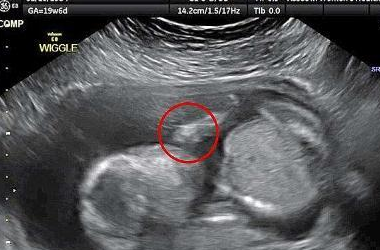

这个宝宝则在打自己的脸,他的动作从超音波照片中看得一清二楚。

812e308d86d95e674b4830cdc8937477.png